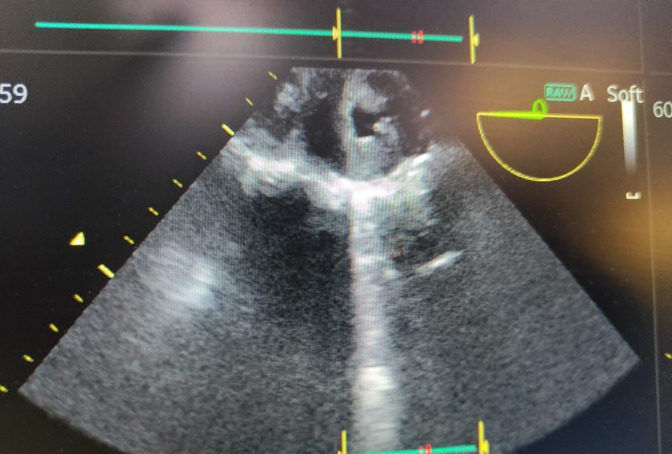

Background. The microbial infection of the endocardium, popularly known as Infective Endocarditis (IE), is typically classified on the basis of anatomy, valve nativity and its associated microbiology. As per the associated microbiology, Staphylococcus aureus is the most common microorganism responsible for the cause of IE. Even though, the Streptococcus group accounts for a smaller percentage of IE, however this doesn't give us the liberty of ignoring the high mortality and morbidity associated with this pathogen. Case presentation. We report an unusual case of neonatal sepsis, complicated with endocarditis, caused by penicillin resistant Streptococcus parasanguinis . The neonate however died of the same despite all efforts. The said baby was given birth by a mother with gestational diabetes mellitus.